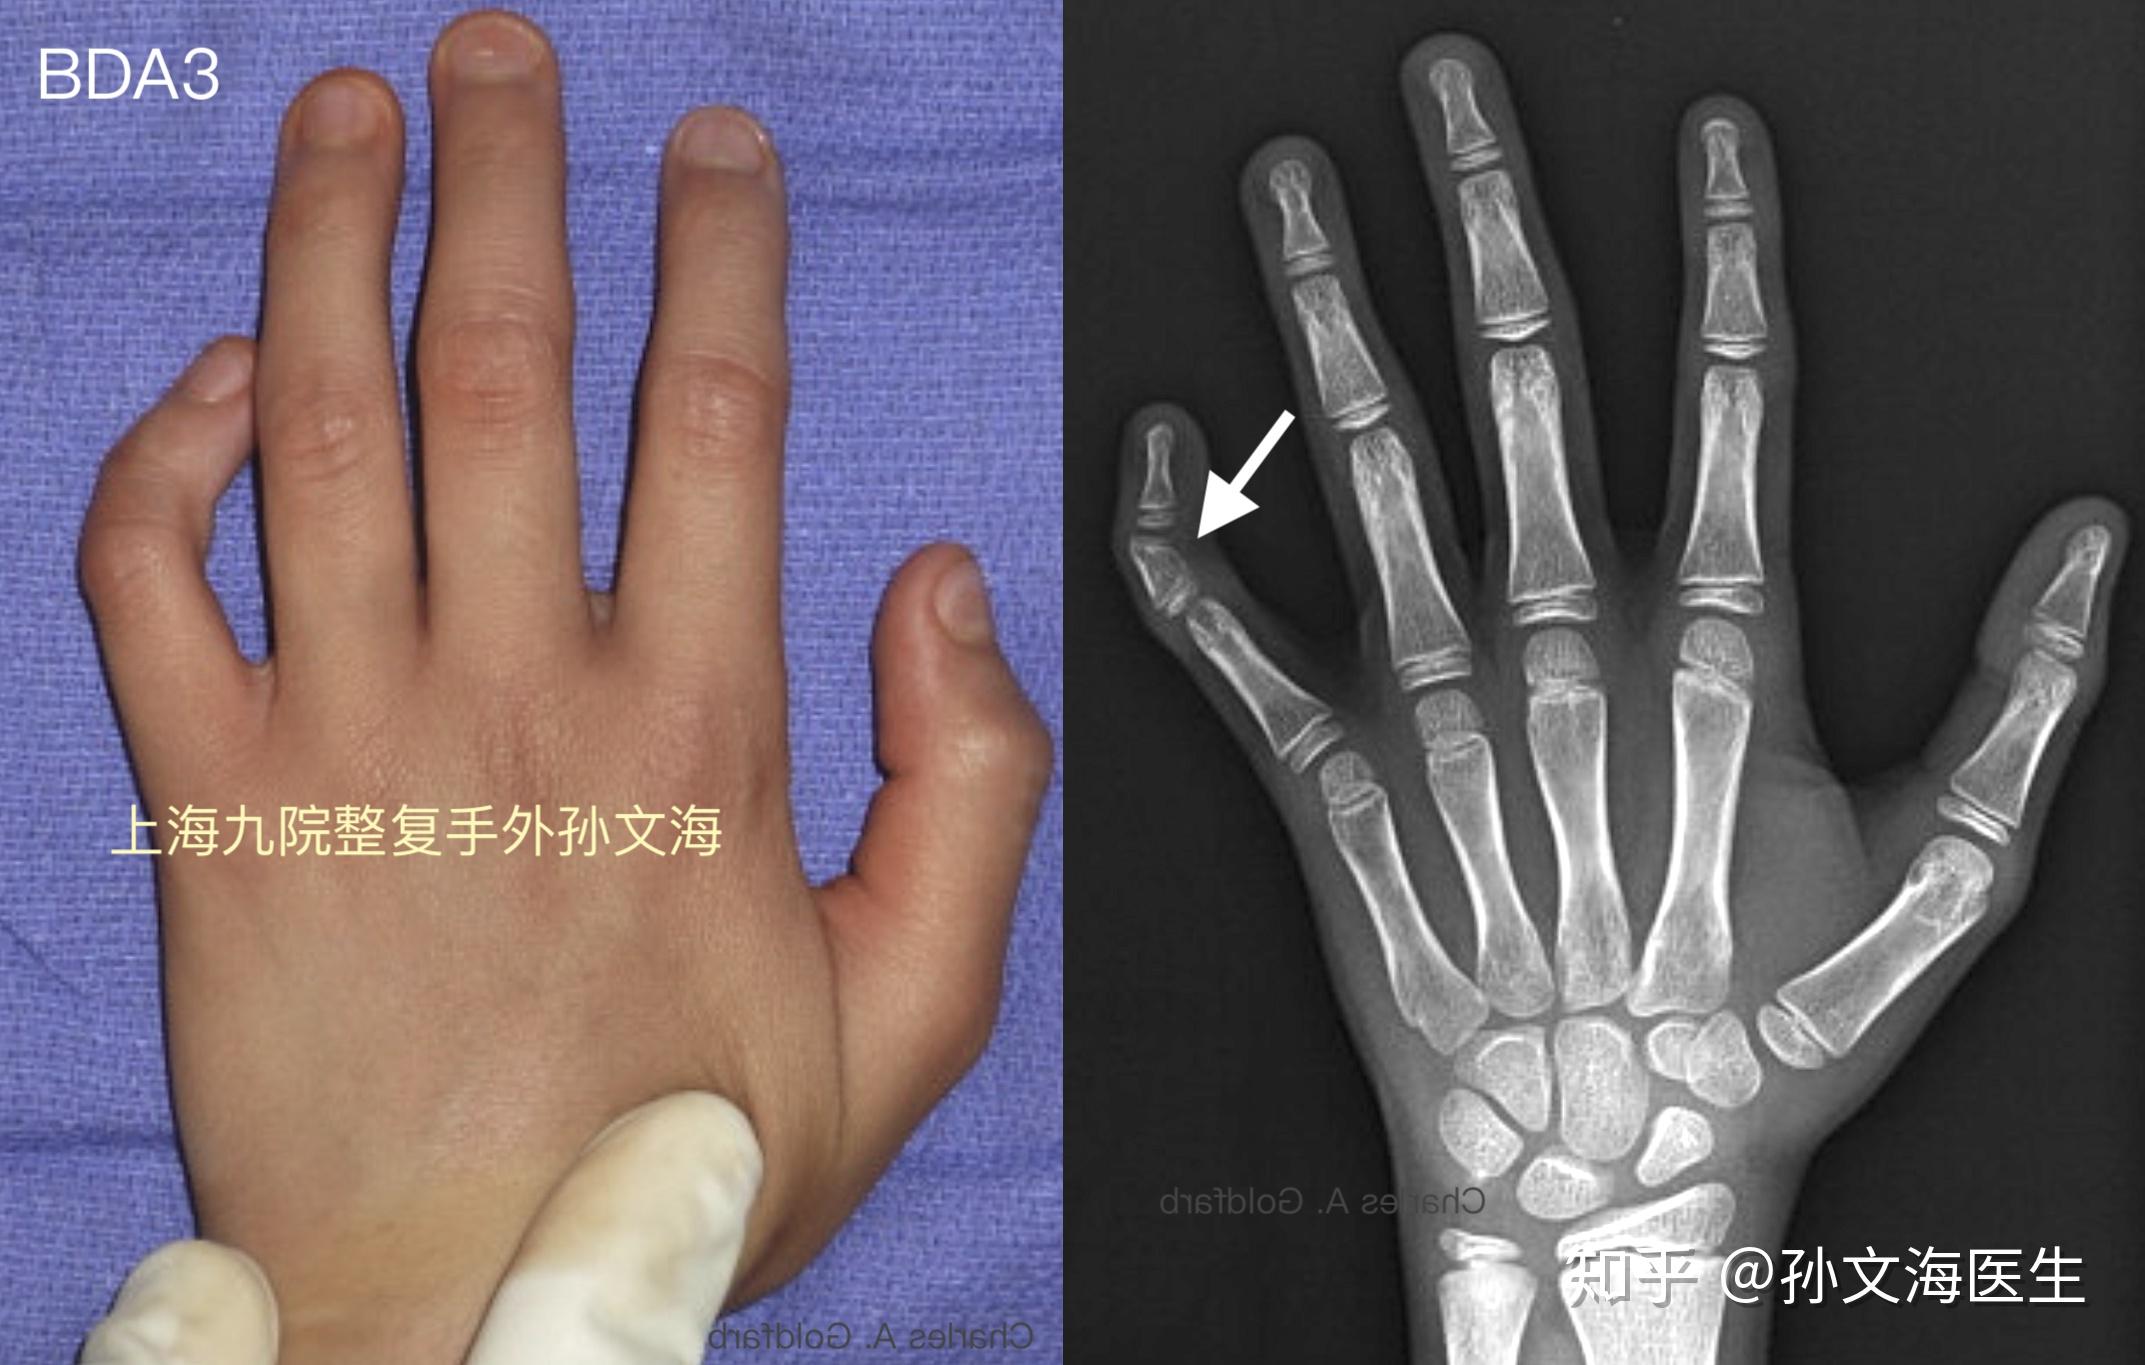

さまざまなタイプの短指症は、影響を受ける骨と指によって分類されます。

タイプA短指症は、中節骨が短縮していることです。これらは、各指の端から 2 番目の指の骨です。タイプAは指の種類によってさらに分類されます。これらは次のとおりです。

• タイプA1: すべての指の中節骨が短くなります。

• タイプA2:人差し指と場合によっては小指が短くなります。

• タイプA3:小指のみを短くしたタイプ。